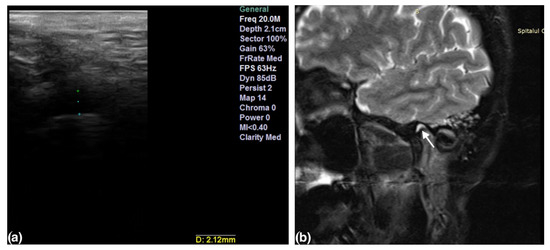

- Talmaceanu, D.; Lenghel, L.M.; Bolog, N.; Stanila, R.P.; Buduru, S.; Leucuta, D.C.; Rotar, H.; Baciut, M.; Baciut, G. High-resolution ultrasonography in assessing temporomandibular joint disc position. Med. Ultrason. 2018, 20, 64–70. [Google Scholar] [CrossRef] [Green Version]

- Talmaceanu, D.; Lenghel, L.M.; Bolog, N.; Buduru, S.; Leucuta, D.; Horatiu, R. High-resolution ultrasound imaging compared to magnetic resonance imaging for temporomandibular joint disorders: An in vivo study. Eur. J. Radiol. 2020, 132, 109921. [Google Scholar] [CrossRef]